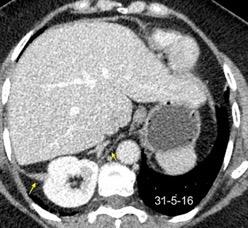

T. mixto de células germinales del testículo izquierdo

Nódulos pulmonares múltiples. (flechas verdes). Masas paratraqueales. (flechas amarillas). Dudoso ensanchamiento retrocrural (flechas negras). sigue….

Ttawfik A et al. Trans-diaphragmatic Pathologies: Anatomical Background and Spread of Disease on cross-sectional Imaging. Current Problems in Diagnostic Radiology. 2021.

T. mixto de células germinales del testículo

izquierdo Metástasis pulmonares. (flechas verdes). Ganglios paratraqueales. (flechas amarillas). Ganglios retroperitoneales (flechas negras)

Tawfik A et al. Trans-diaphragmatic Pathologies: Anatomical Background and Spread of Disease on cross-sectional Imaging. Current Problems in Diagnostic Radiology. 2021.